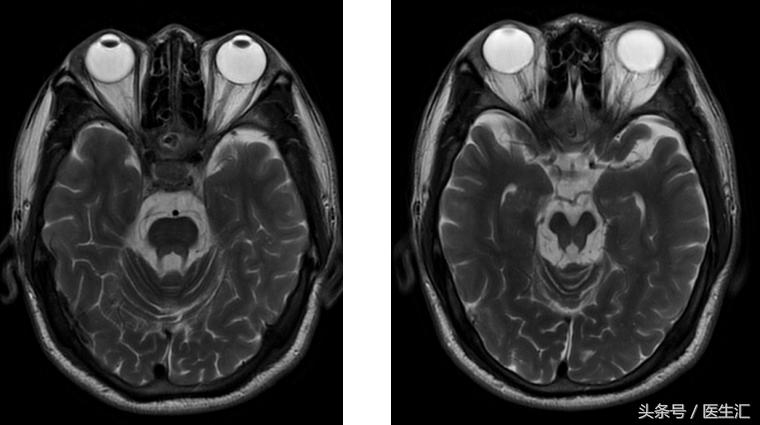

图像资料

定位:锥体外系(震颤)、小脑(步态、共济运动、影像学)

核磁:小脑萎缩、脑干萎缩